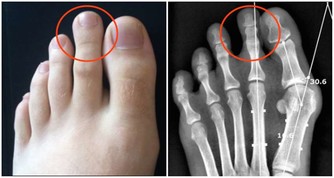

醫生表示,便秘除了有礙發育外,若排便習慣差,長大後還恐形成大腸癌,因此培養定時排便的習慣相當重要,若孩子真的沒辦法在學校上大號,家長得設法讓他們在出門前先上一次,晚上再找時間、也許是洗澡前再排一次,這樣每天至少解便兩次。

針對便秘兒童的飲食,專家建議,家長應幫助孩童建立均衡的飲食習慣,減少食用高動物性脂肪、高蛋白質食物,增加攝取膳食纖維;每日應盡量補充蔬果,也可以多喝水,幫助排便,而喝水量的計算,體重的第1個10公斤乘以100,第2個10公斤乘以50,20公斤以上每公斤乘以20,以1名25公斤的兒童為例,每天至少喝1600 c.c.的水才足夠。